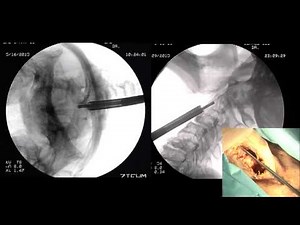

Bone - Transoral Odontoid

Resection - Uncinate

X-ray - Anterior Odontoid

Screw - Odontoid

On Vertebrae - Transoral Odontoid

Fracture Fixation - C1

Fracture Procedure - Atlantoaxial